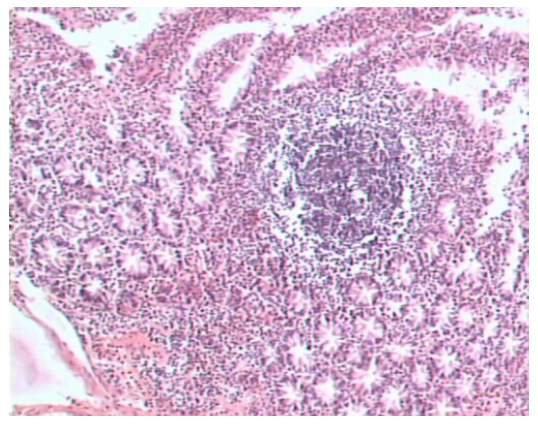

Мышечный слой кишечной стенки был выражен неодинаково в разных срезах, мышечные клетки имели разную толщину, с признаками гипертрофии или атрофии. Но преобладали случаи утолщения мышечного слоя. Отмечены дистрофические изменения мышечных волокон. Изменения межмышечных нервных ганглиев характеризовались уменьшением их в объеме за счет субатрофических процессов, полнокровия периганглионарных зон на фоне умеренного отека (рис. 3).

Рис. 3. Мышечный слой стенки двенадцатиперстной кишки. Уменьшение объема, дистрофические изменения межмышечного нервного ганглия. Окраска гематоксилином и эозином ×10